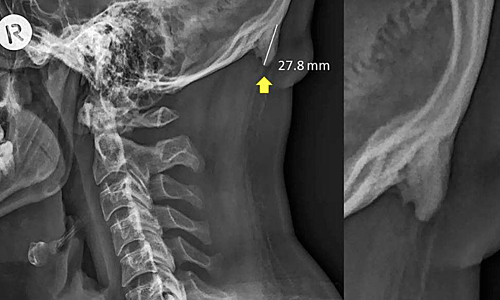

Các nhà khoa học từ University of The Sunshine Coast (Australia) cho biết càng nhiều bệnh nhân trẻ đến bệnh viện với những chiếc gai nhỏ phía sau cổ. Thông thường, chúng có chiều dài khoảng 2,6 cm nhưng một số trường hợp có thể lên đến 3,1 cm.

Trên Scientific Reports, các nhà khoa học University of The Sunshine Coast cho biết hiện tượng hộp sọ "mọc" gai trên còn được gọi là đáy gai nhô bên ngoài vùng chẩm (EEOP), chủ yếu xuất hiện ở người già. Tuy nhiên, khảo sát trên 1.200 tình nguyện viên 18-86 tuổi cho thấy 33% bị EEOP, trong đó phần lớn thuộc nhóm nam giới 18-30 tuổi. Các nhà khoa học cho biết tình trạng này bắt đầu xuất hiện vào những năm 1990 và ngày càng phổ biến.